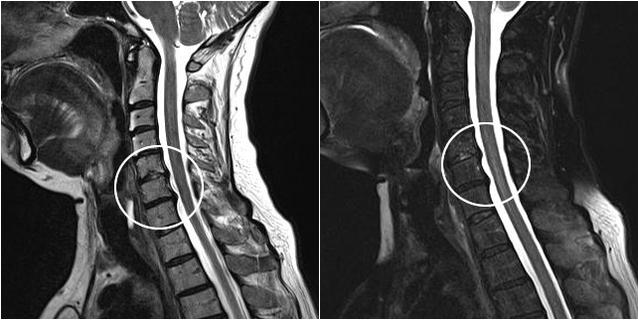

Modern diagnostic methods, including MRI and CT, can most accurately examine the processes of destruction of cartilage and bone tissue.In addition, hernias and other soft tissue defects near the source of disease can be easily diagnosed using this technique.